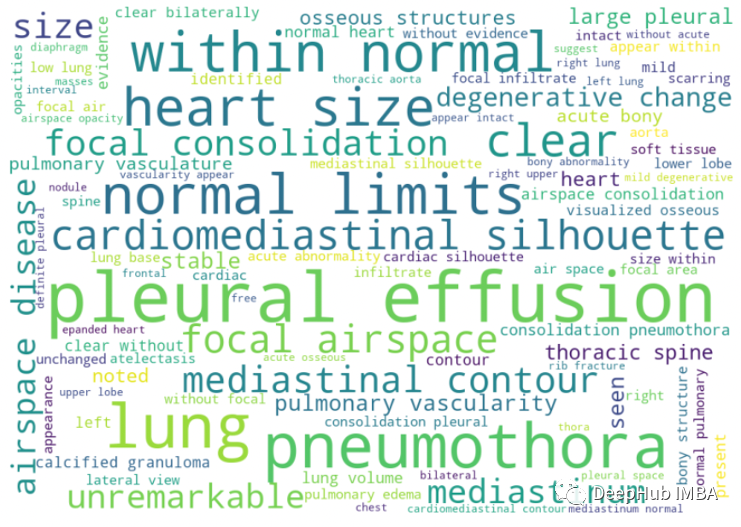

我们可以看到像胸腔积液(pleural effusion),气胸(pneumothora),心脏纵隔轮廓( cardiomediastnal silhouette),yi一般情况下我们认为这些词不是正常词,但这些是医学领域特有的,并且出现的频率很大,说明预处理后看起来很干净。